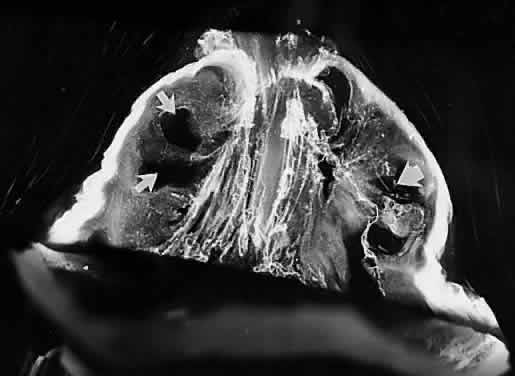

The pathogenesis of retinopathy of prematurity (ROP) begins with birth prior to complete maturation and development of the peripheral retina. Postnatal oxygen administration triggers retinal vasoconstriction with endothelial cell necrosis and vaso-obliteration in response to hyperoxia.127–129 After the discontinuation of supplemental oxygen, arterial pO2 levels return to normal and the obliterated (or at best, highly constricted) vessels are not adequately reperfused, causing the peripheral retina they subserve to become ischemic and release neovascular growth factors. An alternative hypothesis of pathogenesis proposes that spindle cells in the immature peripheral retina are stimulated by excessive amounts of reactive oxygen species, whether related to oxygen therapy and subsequent relative hypoxia or other metabolic circumstances, to release angiogenic growth factors.130 In either case, the result is migration and proliferation of capillary endothelial cells that form new blood vessels at the posterior ridge of tissue between the vascularized and avascular retina. This results in neovascularization arising from the ridge that demarcates the developed posterior retina from the immature peripheral retina (Fig. 6). The new vessels grow into the vitreous body, onto and into the plane that demarcates the interface between the gel vitreous posteriorly (overlying developed retina) and the liquid vitreous anteriorly (overlying immature retina). While somewhat similar to neovascularization in diabetic retinopathy,131 the new vessels in ROP grow farther anteriorly and with greater exuberance. This is perhaps because of the participation of cells of the ocular fetal vasculature, whose apoptosis has been retarded or arrested by the presence of high levels of VEGF.132

Fig. 6. Vitreous pathology in retinopathy of prematurity. The lack of peripheral retinal development, most prominent temporally, results in abnormal secondary vitreous development in this region. Thus, there is liquid vitreous rather than gel in the peripheral fundus. The interface between the normal gel vitreous posteriorly and the liquid vitreous anteriorly causes instability with traction upon the ridge of cells from which new vessels proliferate. The proliferation and membrane formation follows the interface plane between the gel and liquid vitreous compartments, oriented toward the edge of the lens. Traction at the ridge stimulates further vessel proliferation, traction upon the peripheral retina, and ultimately hemorrhage and/or retinal detachment. *, lens; G, gel vitreous (posterior); L, liquid vitreous (anterior). (Courtesy of Maurice Landers, MD)

There are no clearly identified vitreous changes during stages I and II of acute ROP, although this may simply be due to our present inability to detect such abnormalities.133 Indeed, the abundance of reactive oxygen species in the retina and vitreous of premature infants could induce widespread vitreous liquefaction.82 There are also likely to be localized areas of liquid vitreous, particularly at the periphery. At surgery for stage IV-A ROP with retinal detachment, there is a trough in the periphery.134 This structure is most likely the consequence of underlying immature retina in the periphery, with consequent lack of typical gel vitreous synthesis, normally a Müller cell function, overlying the immature retina. The liquid vitreous trough is probably present early in the natural history of disease but goes undetected by present vitreous imaging techniques.133 Such disruption of normal vitreous composition and structure probably alters a number of physiologic processes within the vitreous, including the ability of vitreous to inhibit cellular and vascular invasion.135 Furthermore, the interface between posterior gel vitreous and peripheral liquid vitreous at the ridge causes vitreous traction to be exerted at the retinal ridge.